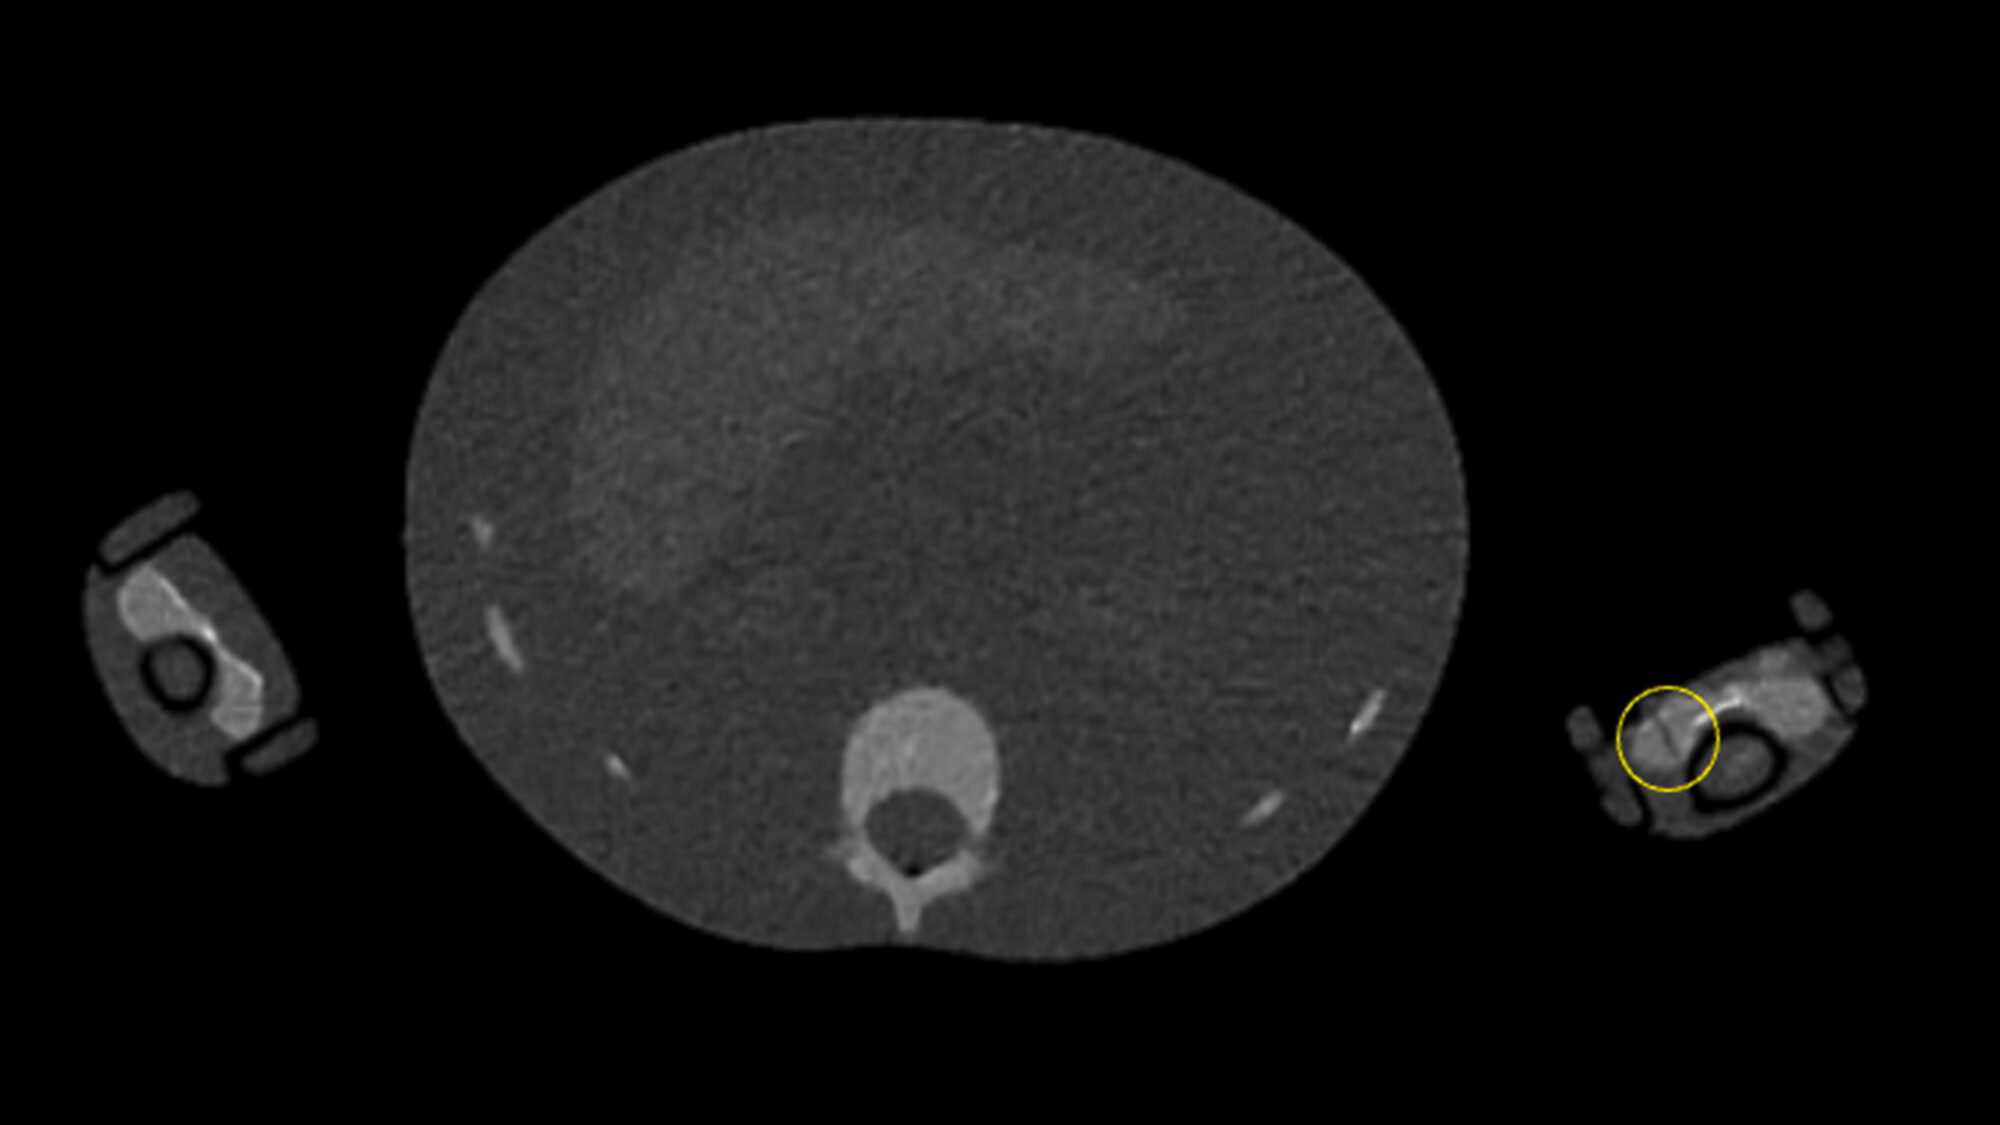

Les 18 MERM de l'étude avaient pour tâche d'identifier les fractures sur un fantôme pédiatrique avec sept sites de fractures (crâne, omoplate gauche, cinquième côte gauche, coude gauche, poignet gauche, fémur gauche, tibia gauche). © E. Doyle et coll. / Radiography 2026 - Elsevier/ CC BY 4.0

Les MERM avaient pour tâche de marquer les fractures à l'aide d'un logiciel de visualisation d'images. Le fantôme utilisé reproduisait le corps d’un enfant de 5 ans avec sept sites de fractures (crâne, omoplate gauche, cinquième côte gauche, coude gauche, poignet gauche, fémur gauche, tibia gauche). Tous les manipulateurs radio de l’étude avaient plus de 10 ans d'expérience, et 67 % d'entre eux travaillaient dans le domaine de l'imagerie pédiatrique.